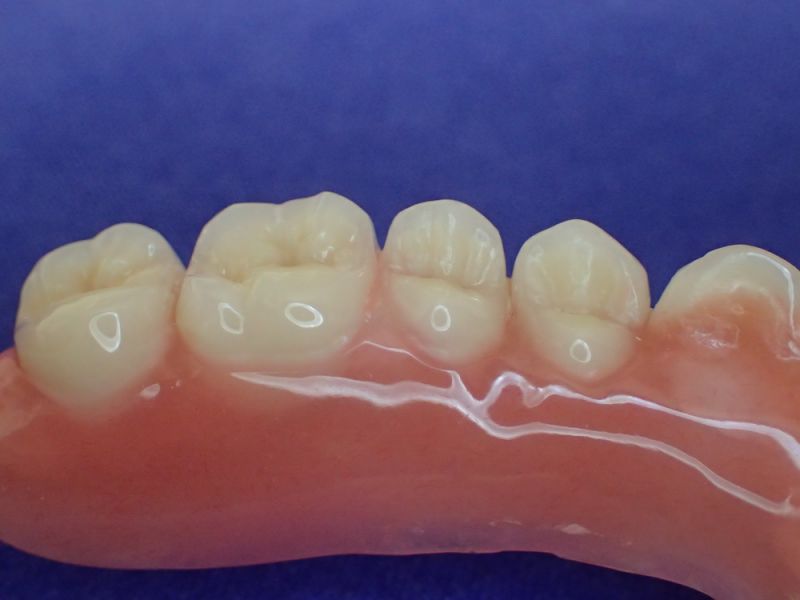

Nach inzwischen 12 jähriger Tragedauer wurden alle Kunststoffteile erneuert, das metallische Grundgeroüst der Arbeit erhalten und die Arbeit befindet sich in einem Zustand, der sich weitgehend an der Ersterstellung orientiert.

Bei derartigen Arbeiten ist es tatsächlich möglich grundlegende Konstruktionsmerkmale einer alten Arbeit zu übernehmen und Verschleißteile aus Kunststoff zu erneuern.

Im Prinzip ist das beliebig oft möglich und für den Patienten mit einer enormen Kostenersparnis verbunden.